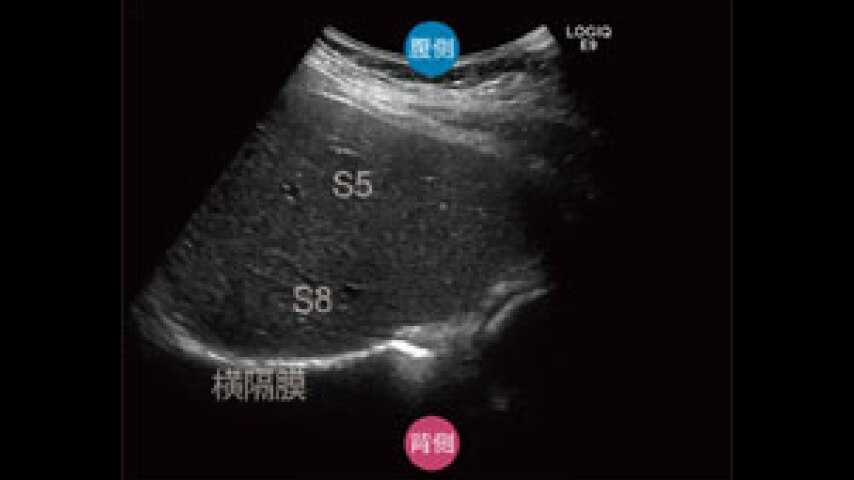

Amazon.co.jp: Nikkei メディカルビデオ VOL.50 30分でわかる,

Amazon.co.jp: Nikkei メディカルビデオ VOL.50 30分でわかる, 腹部エコー|医療法人 さわい消化器クリニック|大腸カメラ・胃,

腹部エコー|医療法人 さわい消化器クリニック|大腸カメラ・胃, m3電子書籍 | 正常画像と並べてわかる腹部エコー,

m3電子書籍 | 正常画像と並べてわかる腹部エコー, Liver | GE HealthCare (Japan),